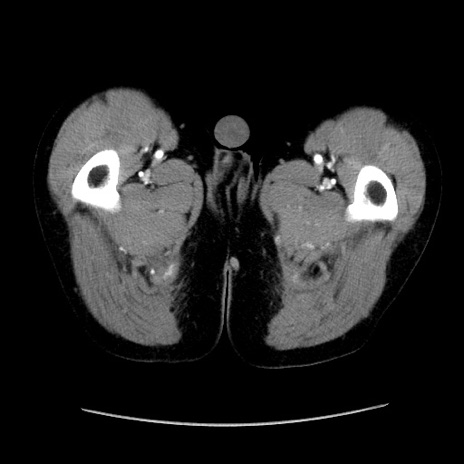

症例37(横断像)

【症例】40歳代 男性

【主訴】腹痛

【現病歴】4時間ほど前に電車に乗車中に臍部上より腹痛出現。徐々に増悪し起立困難となり、救急外来受診。生ものは数日食べていない。今朝お雑煮を食べた。

【身体所見】BT 36.8℃、BP 117/84mmHg、HR 91/min、SpO2 97%、苦悶様、腹部:臍上部広範囲圧痛あり、反跳痛±

【データ】WBC 8100、CRP 0.03